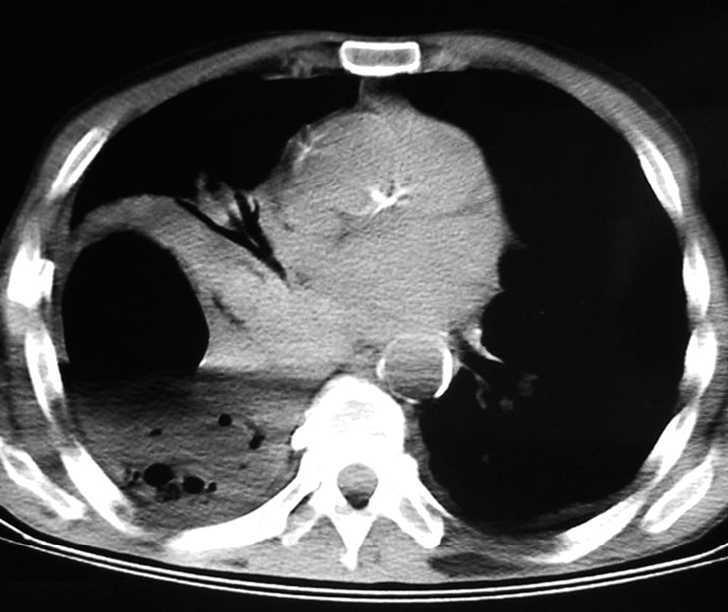

Mujer de 81 años que acudió a urgencias por expectoración hemoptoica, disnea y fiebre de 10 días de evolución. Como antecedentes presentaba bajo peso crónico e historia de reflujo gastroesofágico. En la exploración física estaba consciente, orientada, tenía una prótesis dental, pesaba 34 kg, presentaba fiebre de 38 ºC, la frecuencia respiratoria era de 32 respiraciones/min y la saturación de oxígeno del 94%. En la auscultación pulmonar destacaban crepitantes en el campo medio superior izquierdo. En la analítica practicada en el momento del ingreso la hemoglobina era de 9,4 mg/dl, el hematócrito del 28,8%, la cifra de leucocitos de 6 x 109/l (el 76,3% neutrófilos, un16,1% linfocitos, un 5,5% monocitos y el 1,2% eosinófilos), la de plaquetas de 726 x 109/l, la velocidad de sedimentación de 121 mm/h y la albúmina de 2,1 g/dl; el test de Mantoux fue negativo. La radiografía de tórax mostró una lesión cavitada en el lóbulo superior derecho. Se realizó una tomografía axial computarizada de tórax, que confirmó la presencia de dicha cavitación, de 10 cm de diámetro mayor, con pared interna irregular y nivel hidroaéreo, en el superior derecho (fig. 1). Dos hemocultivos fueron negativos. Se practicó una fibrobroncoscopia sin evidenciar lesiones endobronquiales, y se apreció escasa sangre procedente de bronquio del lóbulo superior izquierdo, con crecimiento en el broncoaspirado de Aeromonas sensible a ciprofloxacino y cefuroxima, y con resistencia a ampicilina. Asimismo, el cultivo en esputo fue positivo para A. hydrophila, con igual antibiograma que el broncoaspirado, y en ambas muestras la tinción de auramina fue negativa. Tanto el cultivo para micobacterias como para hongos fueron negativos. La citología fue negativa para células tumorales. No se realizaron lavado broncoalveolar ni biopsias transbronquiales ante la mala tolerancia, con desaturación de oxígeno importante durante el procedimiento. Se instauró tratamiento antituberculoso inicialmente, que se retiró al recibir el resultado de microbiología, momento en que se cambió a ciprofloxacino y cefuroxima. La mejoría clínica fue evidente, con desaparición de la fiebre, y en un control radiológico realizado a las 3 semanas se apreció disminución de más del 50% de la imagen radiológica.

Fig. 1. Tomografía axial computarizada de tórax en la que se aprecia una lesión cavitada con nivel hidroaéreo en el lóbulo superior derecho.